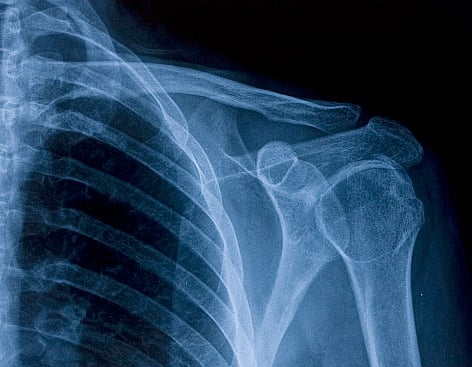

Researchers at the Indian Institutes of Technology Jodhpur (IIT-J) have fostered an Artificial Intelligence (AI) based chest X-ray procedure for Covid-19A screening.

The team proposed a deep learning-based algorithm called COMiT-Net, which learns the abnormalities present in the chest X-Ray images to differentiate between a Covid affected lung and a non-Covid affected lung. The experiment was performed with more than 2,500 chest X-ray images and achieved about 96.80 percent sensitivity.

The AI algorithm not only predicts whether a person has Covid-19 pneumonia, but it is also capable of identifying the infected regions in the lungs, thus making them explainable. The new technique can visually showcase the region which is infected. It interprets only from the lung region.

The AI solution used in this research is explainable from both algorithmic and medical points of view. The team has detailed the technique in a research paper published in the journal Pattern Recognition (Volume 122). With the increasing number of Covid-19 cases across various waves around the globe, countries have faced challenges with the limited availability of testing kits and processing centers in remote areas. This has been the key motivation for researchers to find alternate methods of testing which are reliable, easily accessible, and faster.